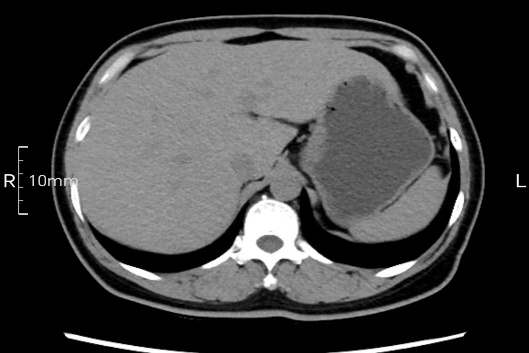

看看下面三幅便知遵醫(yī)囑的重要性。

完美禁食且喝飽飽,胃壁完美展現(xiàn)。